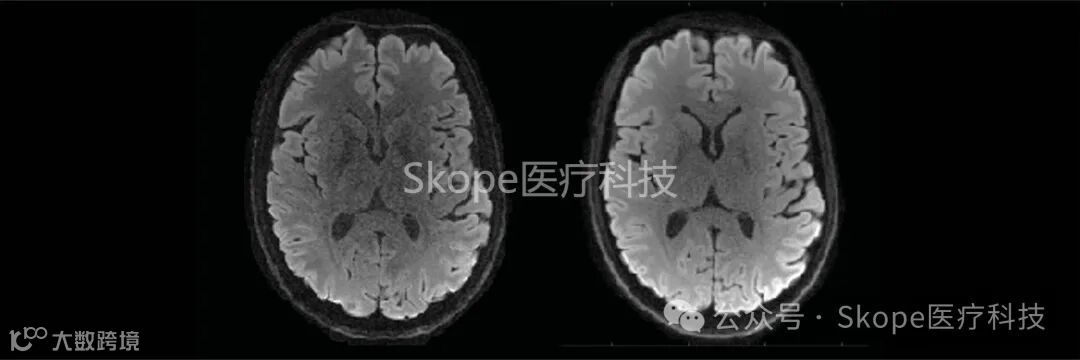

实际上,由强扩散梯度引起的涡流电流是扩散加权成像领域中图像伪影的最重要来源。可以使用涡流电流抵消策略来减轻这些效应,但代价是较长的回波时间和较低的信噪比。通过监测读数轨迹,您可以放弃这些补偿方法并简化采集过程。在下面所示的示例中,将一个EPI和一个带有单个重调谐RF脉冲的螺旋扩散加权采集进行了比较。螺旋读数的较短回波时间(TE)直接转化为更高的信噪比,这可以用来换取更高的空间分辨率。

Further reading: Lee et al. (2020), ETH Zurich. On the signal‐to‐noise ratio benefit of spiral acquisition in diffusion MRI.

*使用skope-i重建的高分辨率EPI(TE = 71毫秒)(左)和螺旋(TE = 42毫秒)(右)平均DWI图像 (来源:Skope)

Courtesy Yoo Jin Lee, IBT ETH Zurich and University of Zurich.